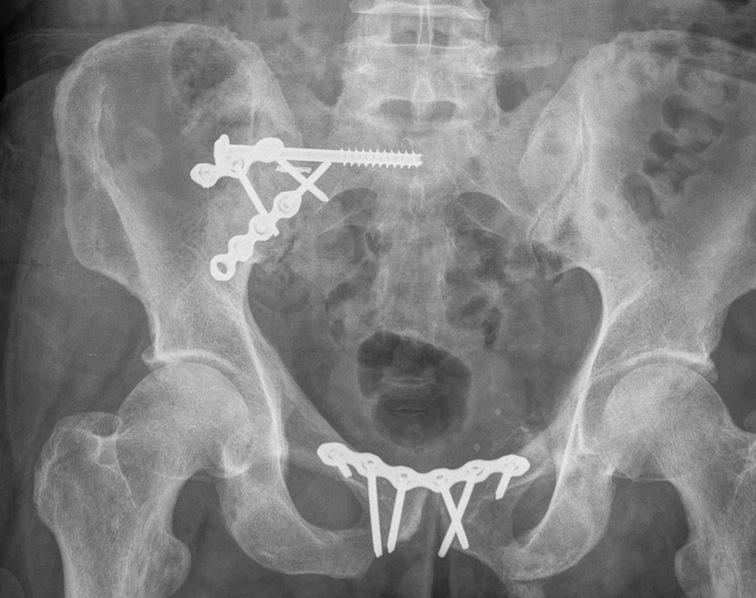

Operative management

Technique

Posterior fixation

Anterior fixation if unstable or bilateral pubic rami fractures

Percutaneous sacroiliac screws

Posterior approach + / - plates

Anterior fixation

Indications

- instability following posterior fixation

- bilateral pubic rami fractures

Options

- plate - modified stoppa

- percutaneous ramus screws

- external fixation

LC-1 with anterior external fixation Plating of bilateral pubic rami fractures